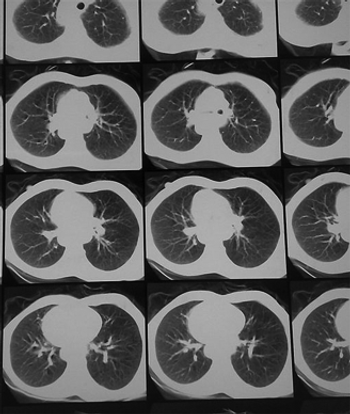

A retrospective analysis suggested that a declining proportion of patients with lung cancer would meet the criteria for undergoing low-dose CT screening.

This one-act play features a patient, former smoker, navigating the CMS rules for lung cancer CT screening in a shared decision-making session with his doctor.